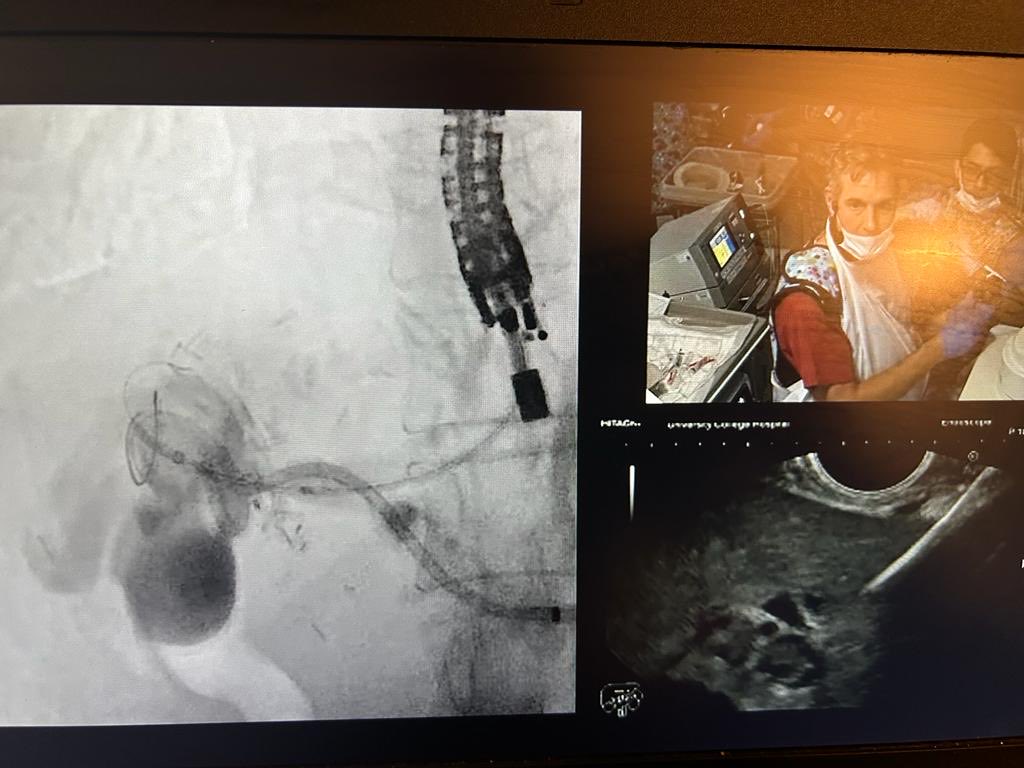

Starting out in EUS is hard! And trying to work out the FNA needle when you’re trying to keep your eye on the target can have even harder! We are grateful to @drgavinoz for putting together this explainer in run up to @LLEndoscopy youtu.be/so7AxJJeR0U